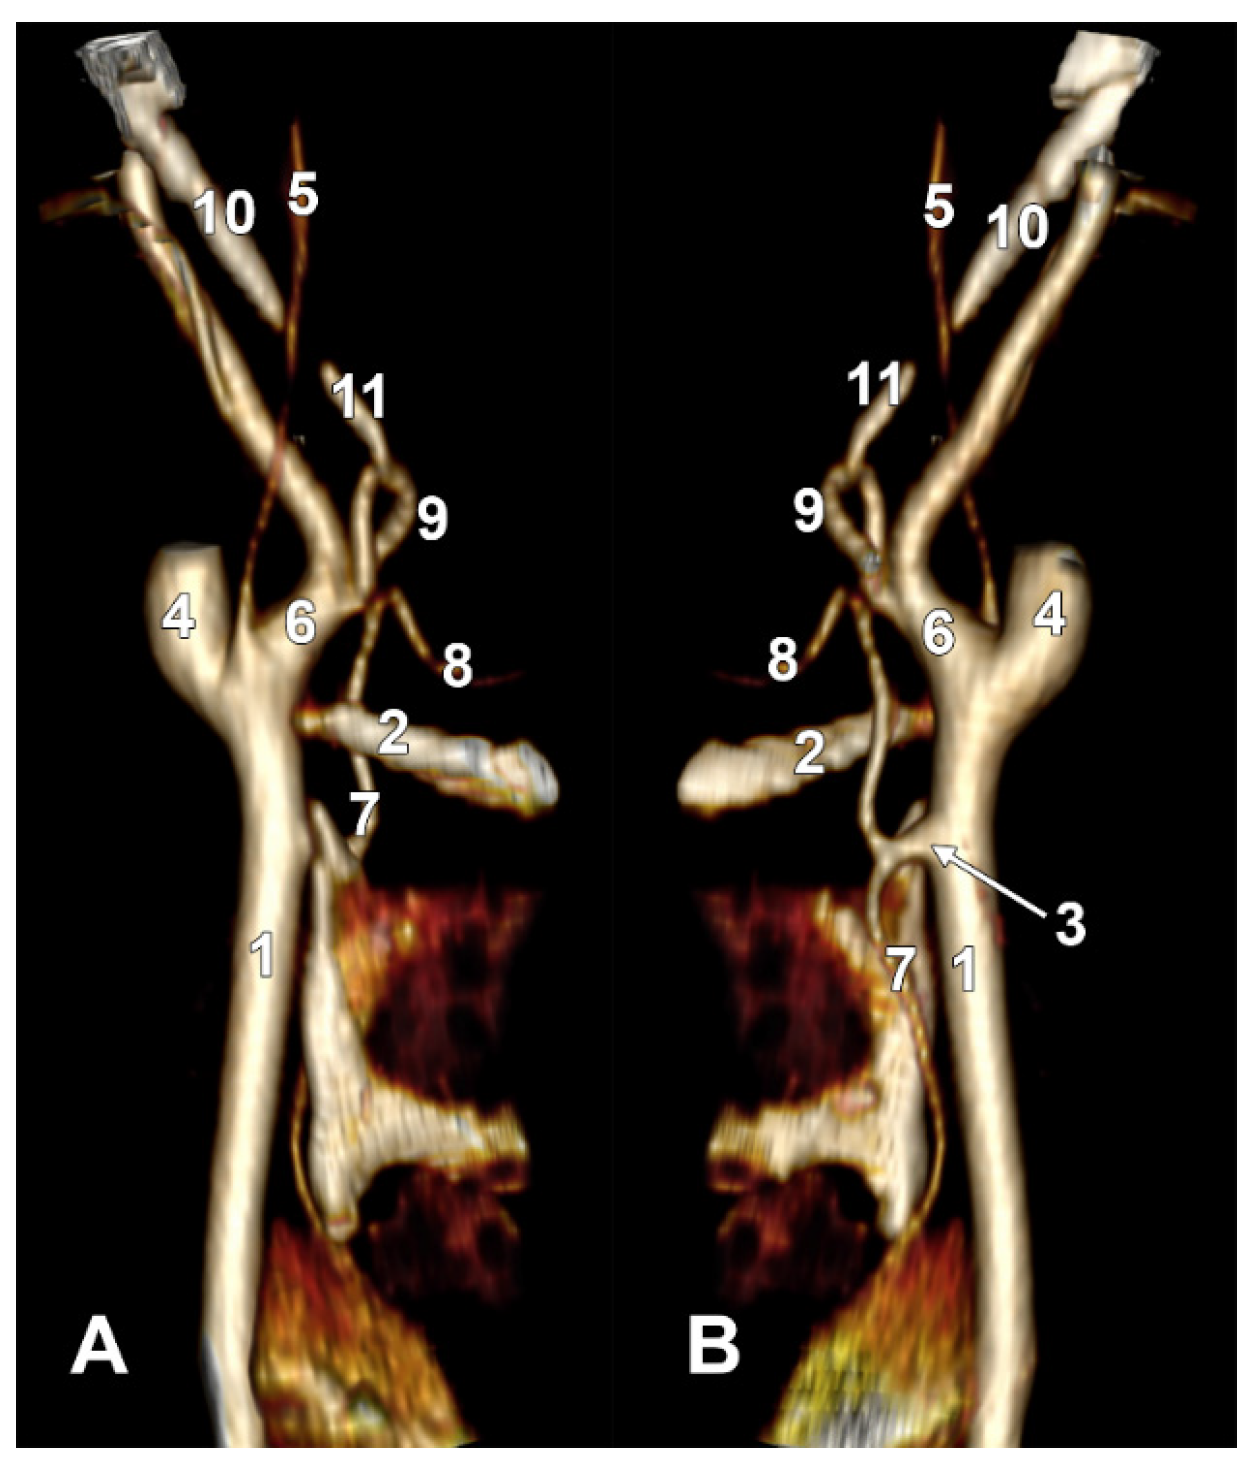

Figure 8. Long inferior petrosal sinus (arrowheads). Internal carotid origin of the ascending pharyngeal artery. Right side. (A) Anterolateral view. (B) Anteromedial view. 1. Common carotid artery; 2. internal jugular vein; 3. internal carotid artery; 4. external carotid artery; 5. superior thyroid artery; 6. lingual artery; 7. facial artery; 8. ascending pharyngeal artery; 9. styloid process; 10. body of the hyoid.

On the right side (Figure 7 and Figure 8), a 4.23 cm long styloid process was found, with a medial inclination of 72.4°. It crossed anteriorly, above the transverse process of the atlas, two veins: laterally—the internal jugular (IJV) vein, which had a transverse diameter of 5.94 mm, and medially—a long inferior petrosal sinus (IPS), with a transverse diameter of 3.15 mm. The IJV continued laterally to the transverse process of the atlas, and the inferior petrosal sinus, anterior to it. It was observed that the compression of the IJV occurs between the transverse process of the atlas and the posterior aspect of the digastric muscle. Also, the IPS appeared compressed at this level. The IJV had a minimum diameter of 1.21 mm, and the IPS had a minimum diameter of 1.08 mm. The IPS crossed laterally the ICA and APA, which, in turn, originated from the ICA (type IV), and continued medial to the ECA, crossed the origin of the FA, and descended anterior to the ECA, over the initial loop of the LA. The IPS and ECA coursed on the lateral side of the greater hyoid horn. Inferior to the hyoid, the IPS crossed the STA laterally and continued obliquely posteroinferiorly over the CCA, emptying into the IJV at 3.59 cm inferior to the CB. The APA on that side arose from the anteromedial wall of the origin of the ICA, at the hyoid level.